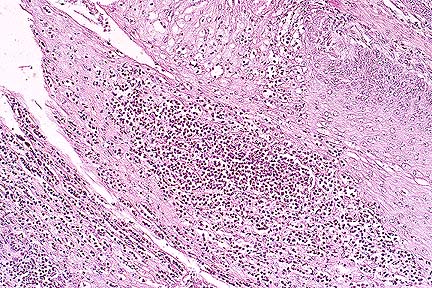

Dilated colonic gland lined by attentuated epithelium surrounded by a mixed population of macrophages and neutrophils in a pig with salmonellosis. (HE, 200X, 64K)

1. Colitis, erosive, superficial, purulent, multifocal with nematodes compatible with Trichuris suis.

2. Colitis, purulent, deep, multifocal-coalescing, chronic.

Etiology: 1. Trichuris suis 2. Serogroup B Salmonella sp.

Trichuris suis is an important cause of diarrhea and poor growth in pigs raised in dirt lots. When infection is heavy, the fecal material often contains blood and mucus and there are erosions and hemorrhages in the cecum and proximal colon. As they are in this case, the nematodes are closely associated with or embedded into the colonic mucosa. In these sections, there are many foci in which the superficial mucosa is eroded and there is migration of neutrophils into the colonic lumen. Balantidium coli are often present in association with the T. suis and the crypts are filled with mucus. These changes, without the nematodes, are also seen with swine dysentery caused by Serpulina hyodysenteriae. We did not find any nematodes that contained the characteristic bipolar ova, indicating that the infection was probably not patent. In addition to the superficial colitis, most colon sections contain dilated crypts that are prolapsed into the submucosa and filled with neutrophils and mucus. In the submucosa there are multiple, coalescing infiltrates of neutrophils, macrophages, and lymphocytes. This submucosal inflammation is indicative of infection by an invasive organism and is compatible with the group B Salmonella sp. that was isolated.

AFIP Diagnosis: Cecum and colon (per contributor): Typhlocolitis, subacute, diffuse, moderate, with erosions, glandular herniation and abscessation, adult trichurid nematodes, and Balantidium coli, cross breed, porcine.

Balantidium coli is a large ciliated protozoan with both a macronucleus and micronucleus. It is a commensal parasite in the cecum and colon of swine but often complicates necrotizing or ulcerative diseases of the cecum and colon, especially trichurid infection, intestinal adenomatosis, swine dysentery, and salmonellosis.

In swine, salmonellosis usually occurs in 2 to 4-month-old feeder pigs. There are three syndromes associated with salmonellosis in swine: a septicemic disease associated with S. cholerasuis, enterocolitis and necrotizing proctitis associated with S. typhimurium, and caseous tonsillitis, lymphadenitis, and ulcerative colitis associated with S. typhisuis.